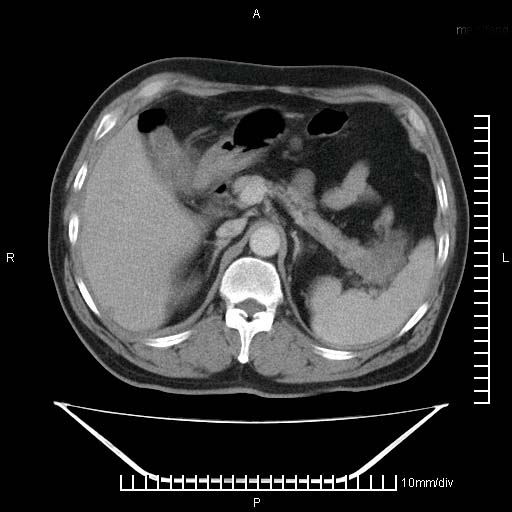

标题: CT25082:肝脏增强:男性,70岁 [打印本页]

标题: CT25082:肝脏增强:男性,70岁

患者以心脏疾病收住院,腹部无明显症状,b超查肝脏有占位。

增强效果不理想。考虑转移,胆囊壁明显增厚,不排除胆囊癌肝转移。

牛眼征,中心坏死无强化,外缘强化,最外缘又见低密度,考虑转移,与脓肿鉴别

肝内多发转移瘤,右下肺炎症并少量胸水。胃壁增厚建议胃镜,胰尾部“病变”为肠管。

1)肝脏多发性转移瘤(不排除胰尾癌转移所致可能)。2)腹水。3)右侧少量胸腔积液。

ct25082 结果:转移瘤

外院mr结果:胰尾恶性占位。